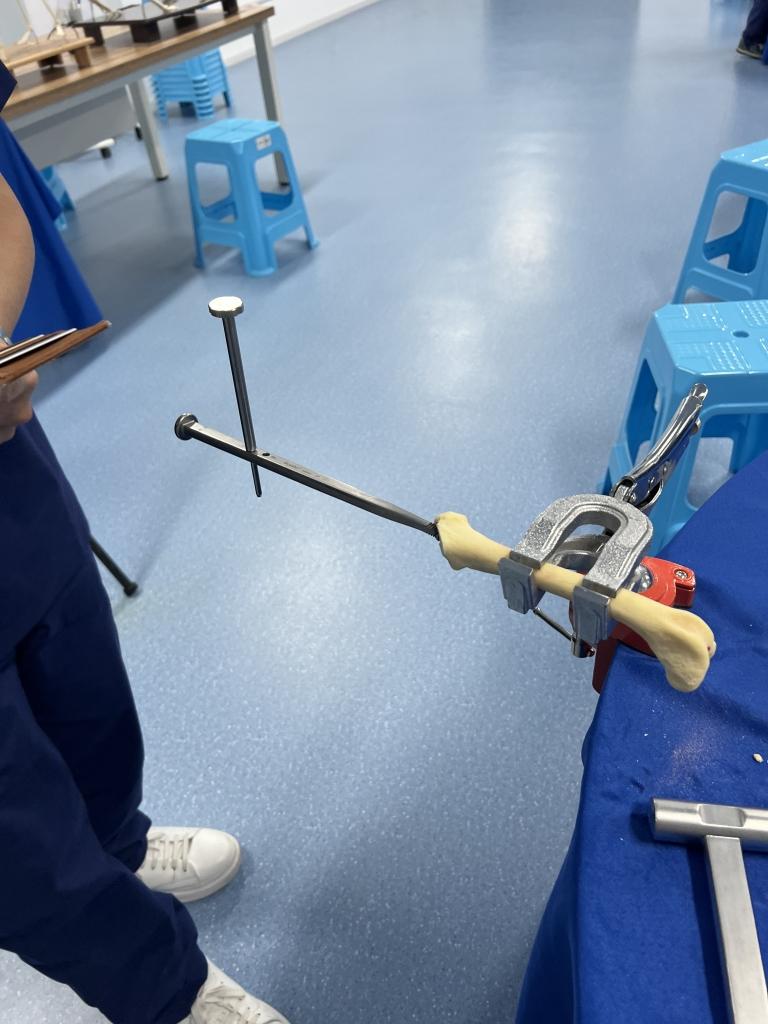

実際の骨模型を使用した人工股関節の設置トレーニング

リーミング(臼蓋の形成)の手技

ステムを真っ直ぐ挿入するコツ

小型犬で特に注意すべき解剖学的ポイント

術中の合併症を回避するための実践的な技術